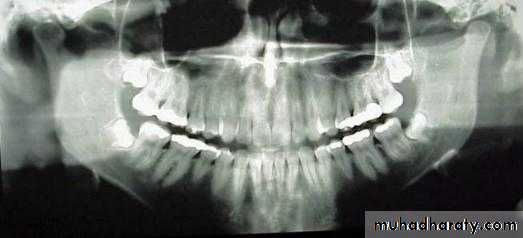

ANGLE’S CLASSIFICATION OF MALOCCLUSION

In 1899 Edward H. Angle published the first classification of malocclusion.

The classifications are based on the relationship of the mesiobuccal cusp of the maxillary first molar and the buccal groove of the mandibular first molar.